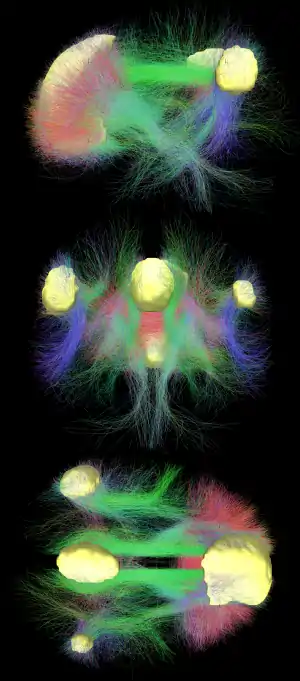

Diffusion MRI imaging shows white matter tracts connecting different areas of the DMN together.[20] The structural connections found from diffusion MRI imaging and the functional correlations from resting state fMRI show the highest level of overlap and agreement within the DMN areas.[1] This provides evidence that neurons in the DMN regions are linked to each other through large tracts of axons and this causes activity in these areas to be correlated with one another. From the point of view of effective connectivity, many studies have attempted to shed some light using dynamic causal modeling, with inconsistent results. However, directionality from the medial prefrontal cortex towards the posterior cingulate gyrus seems confirmed in multiple studies, and the inconsistent results appear to be related to small sample size analysis. [26]